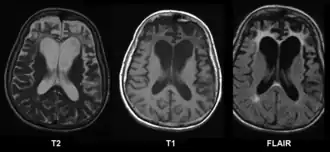

De ziekte van Pick is een vorm van dementie die zich meestal openbaart op relatief jonge leeftijd (45-60 jaar). De ziekte is genoemd naar de Duitse neuroloog Arnold Pick, die voor het eerst een patiënt met deze ziekte beschreef in 1892. In tegenstelling tot de ziekte van Alzheimer die de gehele hersenen aantast, beperkt deze soort van dementie zich tot de frontale kwab van de grote hersenen.